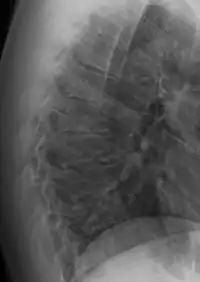

Scheuermann's disease

Scheuermann's disease is a self-limiting skeletal disorder of childhood. Scheuermann's disease describes a condition where the vertebrae grow unevenly with respect to the sagittal plane; that is, the posterior angle is often greater than the anterior. This uneven growth results in the signature "wedging" shape of the vertebrae, causing kyphosis. It is named after Danish surgeon Holger Scheuermann.[3][4][5]

Diagnosis is typically by medical imaging. The degree of kyphosis can be measured by Cobb's angle and sagittal balance.